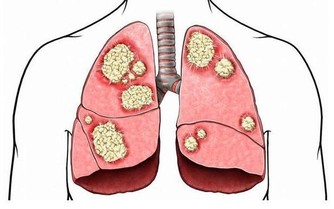

一說起尿毒症可能大家現在都不太陌生,尿毒症是指身體不能通過腎臟產生尿液,把身體代謝所產生的廢物,還有多餘的水分排出體外而引起的毒害,尿毒症是腎功能下降

結語:尿毒症對身體的傷害是毀滅性的,目前的醫療水平無法徹底根治尿毒症。那麼我們就應該防患於未然,改變不良的生活習慣,這樣才能更好的保護自己的腎臟。